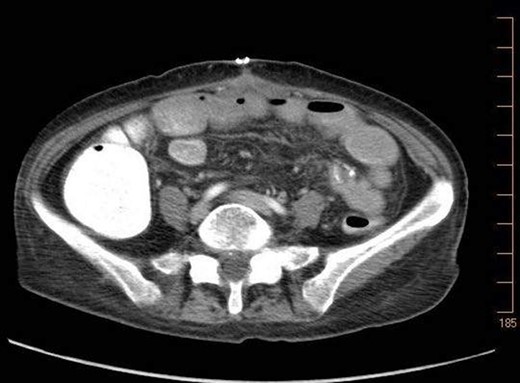

A 57-year-old non-toxic appearing female with a medical history of diverticulosis and malnutrition, and a surgical history significant for small bowel obstruction due to jejunal lymphangioma status post exploratory laparotomy and resection of bowel (2.2018). This patient presents with epigastric pain ×2 days with radiation to left upper quadrant and nausea with emesis, concerning for obstruction. In the Emergency Department, the patient was non-toxic appearing, hemodynamically stable, with no leukocytosis (7.4), or elevated lactic acid (1.2). Imaging, XR (Fig. 1) and CTAP (Fig. 2), demonstrating SBO with free air concern for perforated viscus. The concern for free air on imaging, in the setting of abdominal pain with symptoms of obstruction, mandated an operative intervention. On 7.5.18 the patient underwent exploratory laparotomy and was found to have emphysema of proximal jejunum, and underwent 125 cm resection of jejunum (Figs 3 and 4). Pathology of the specimen demonstrated multiple air filled cystic serosal nodules consistent with PCI (Figs 3 and 4, Supplementary Fig. S7).

Multiple air filled cystic serosal nodules consistent with pneumatosis cystoides intestinalis.